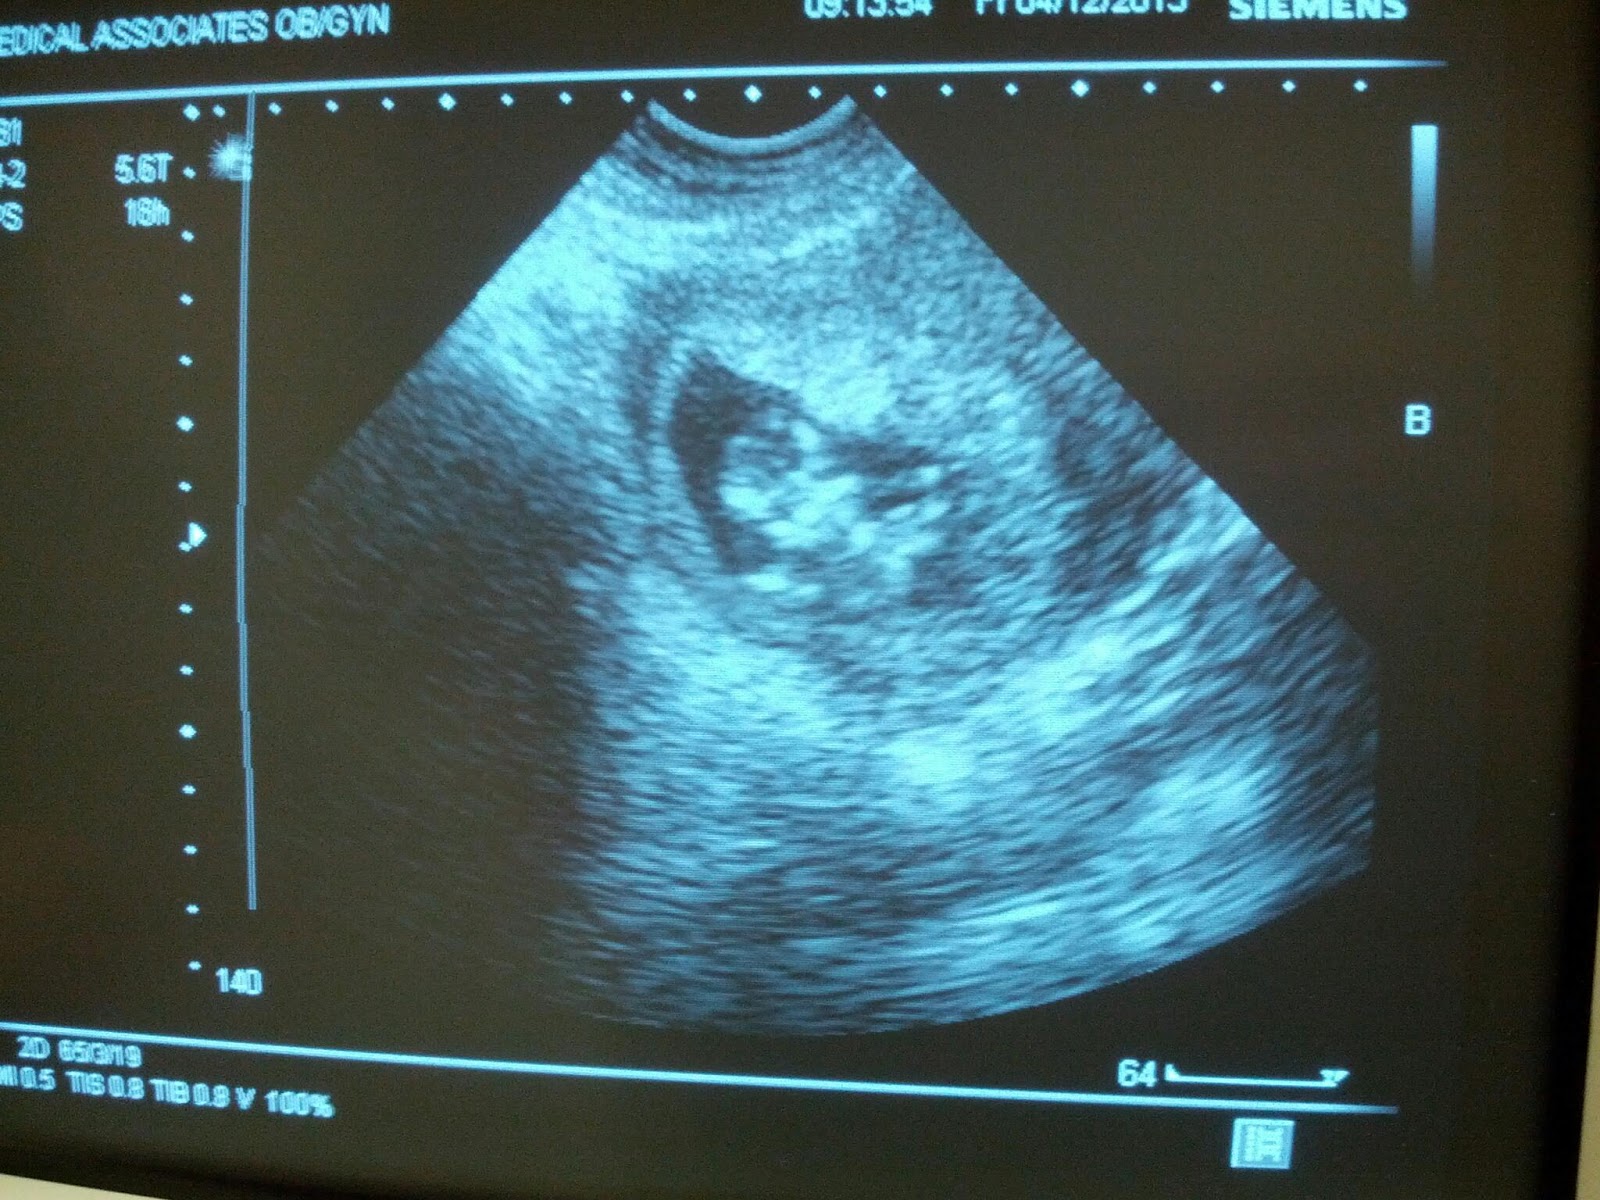

The appt went great. Baby was fine, we got some quick pics and afterward we told our families the big news.

Holy crap tomorrow's the day. 12 weeks. The doctors appointment is in the morning and I'm sure it'll be a quick check and then "see you in a month!".

3/25/2011 - 11w5d (12 week appt): U/S #5 showed more growth and strong heartbeat with tons of movement.